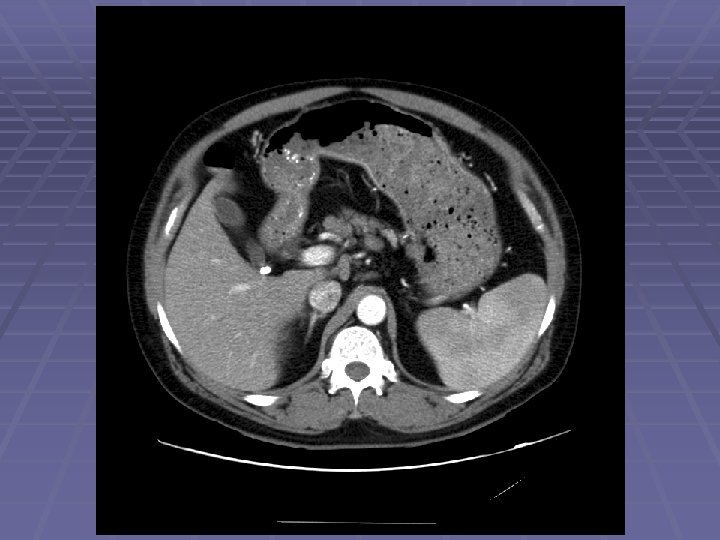

Pancreatic Mass at CT